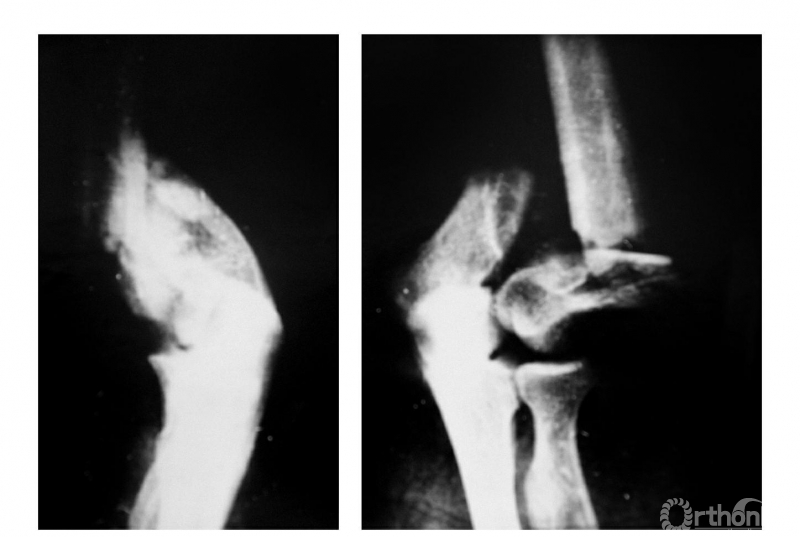

例2:肱骨髁间骨折并尺偏,内外髁骨块严重分离并旋转(Ⅲ型)(图2)。

图2